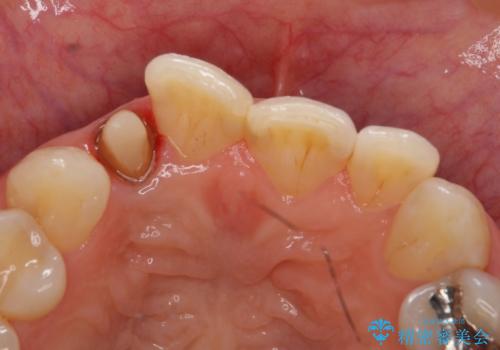

- 右上2番目の歯の変色が気になるといらっしゃった方の症例です。

再根管治療終了後、オールセラミッククラウンによる補綴を行いました。